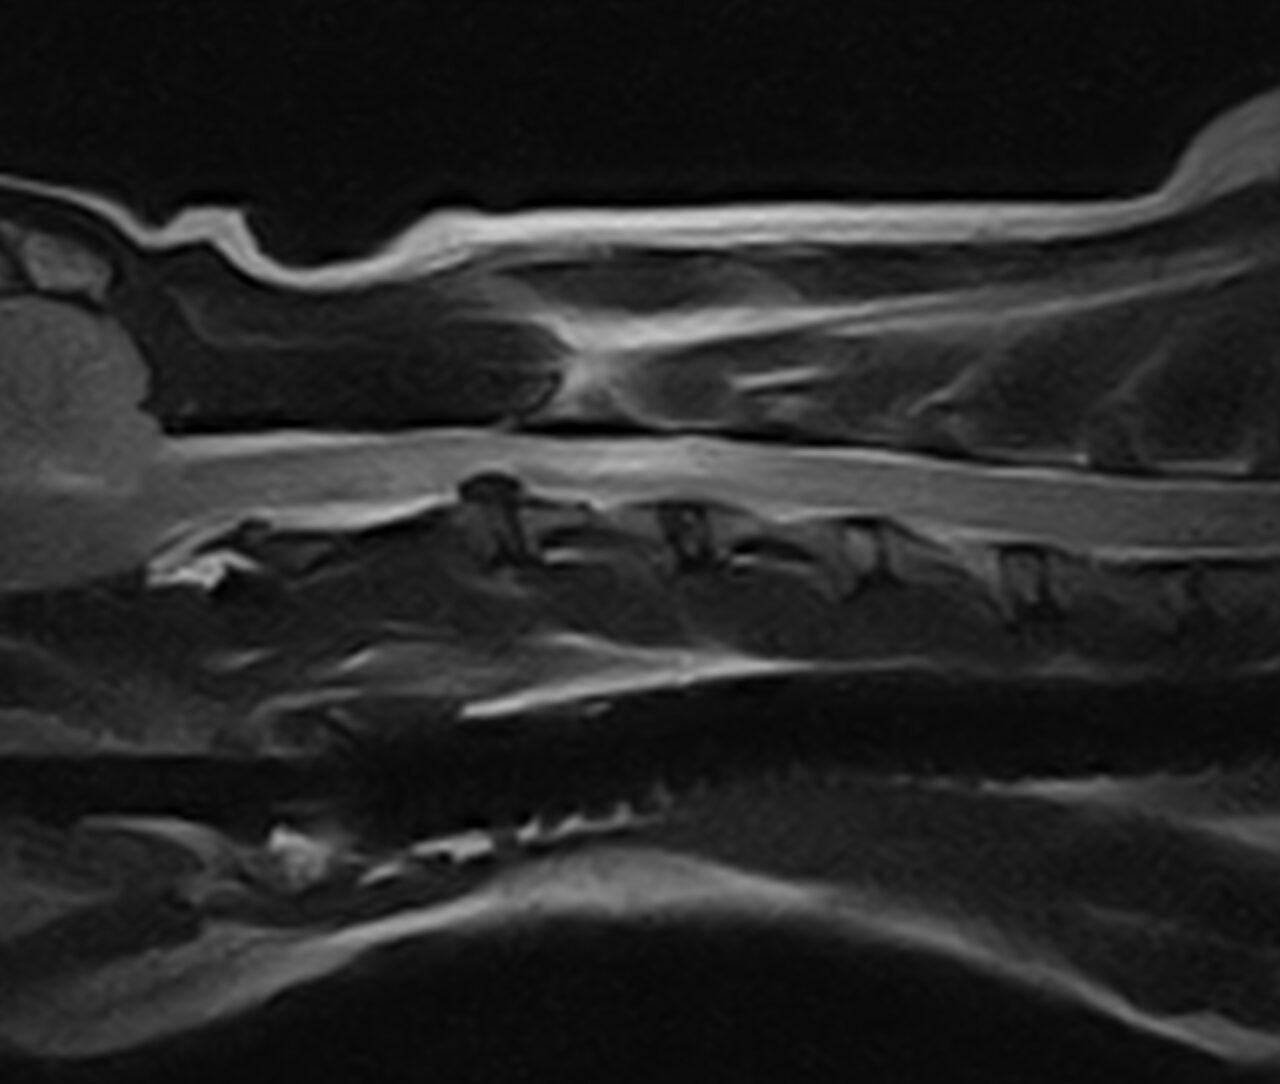

頸部椎間板ヘルニア

腰のヘルニアが疑われていましたが、歩様観察を行うと前肢にも運動失調症状が確認され、頸部脊髄疾患と判断しMRI撮影を行いました。

第二頸椎と第三頸椎の椎間板ヘルニアであり、翌日ベントラルスロットによる脊髄圧迫解除を行いました。